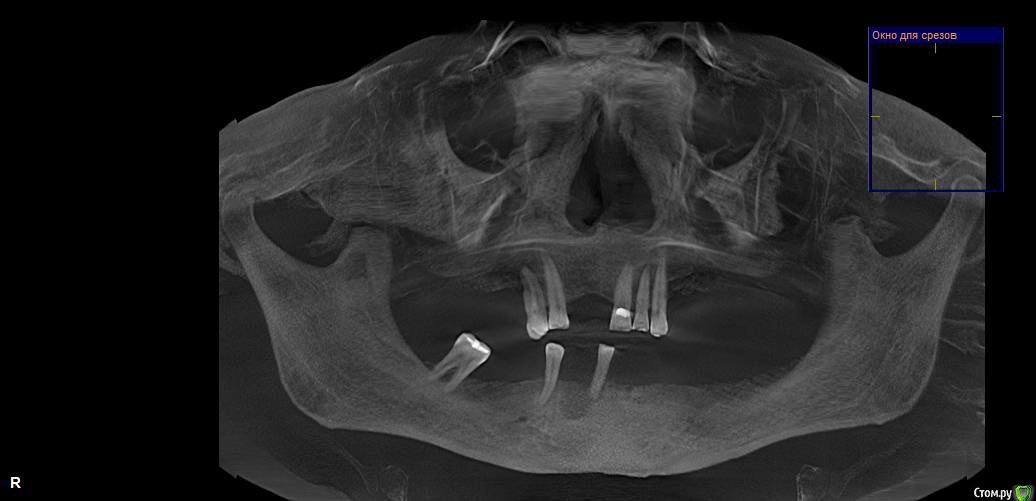

FuturePatient Опубликовано 2 мая, 2017 Поделиться Опубликовано 2 мая, 2017 (изменено) Доброго времени, уважаемые. Есть ли смысл оставлять что-то вверху (существует варианты такого мнения)? Если есть, то в чём? Хотя они там крепко сидят, пока. Полагаю, рано или поздно оставшиеся последуют за ушедшими ранее. И тогда опять по кругу. Или всё же удалить сразу всё, имплантировать и сооружать конструкции полностью верх /низ? Утверждается, внизу кости достаточно, вверху может понадобится небольшой синус-лифтинг. Какие могут быть необходимые и достаточные варианты имплантации в данном случае для восстановления максимальной функциональности и всего прочего? От чего это (варианты) зависит – только от толщины кошелька или есть/могут быть какие-то другие объективные для моего случая аргументы? И таки может кто-то посоветует Доктора (теперь уже уверенно) имплантолога, кто взялся бы за мой случай? Соотв. обращение 20.04.17 было размещено в соотв. теме: http://forum.stom.ru/topic/16116-posovetujte-khirurgaimplantologa/page-54 Разумеется, не оставляю собственные попытки. Не то что б привередлив, но пока как-то не везёт. Понимаю, что искать надо доктора, но общаться-то приходится и с клиниками. Не здесь же рассказывать, сами знаете… Благодарю всех, кто откликнется по любому из представленных вопросов. Изменено 2 мая, 2017 пользователем FuturePatient Ссылка на комментарий

колесников Опубликовано 2 мая, 2017 Поделиться Опубликовано 2 мая, 2017 Если зубы не удалять,план лечения будет более дорогим,сложным и длительным. Большие дефекты в боковых областях на вч,мне видится съёмный протез с опорой на 4 импланта . Точно можно сказать только после диагностики прикуса и 3д снимка. Ссылка на комментарий